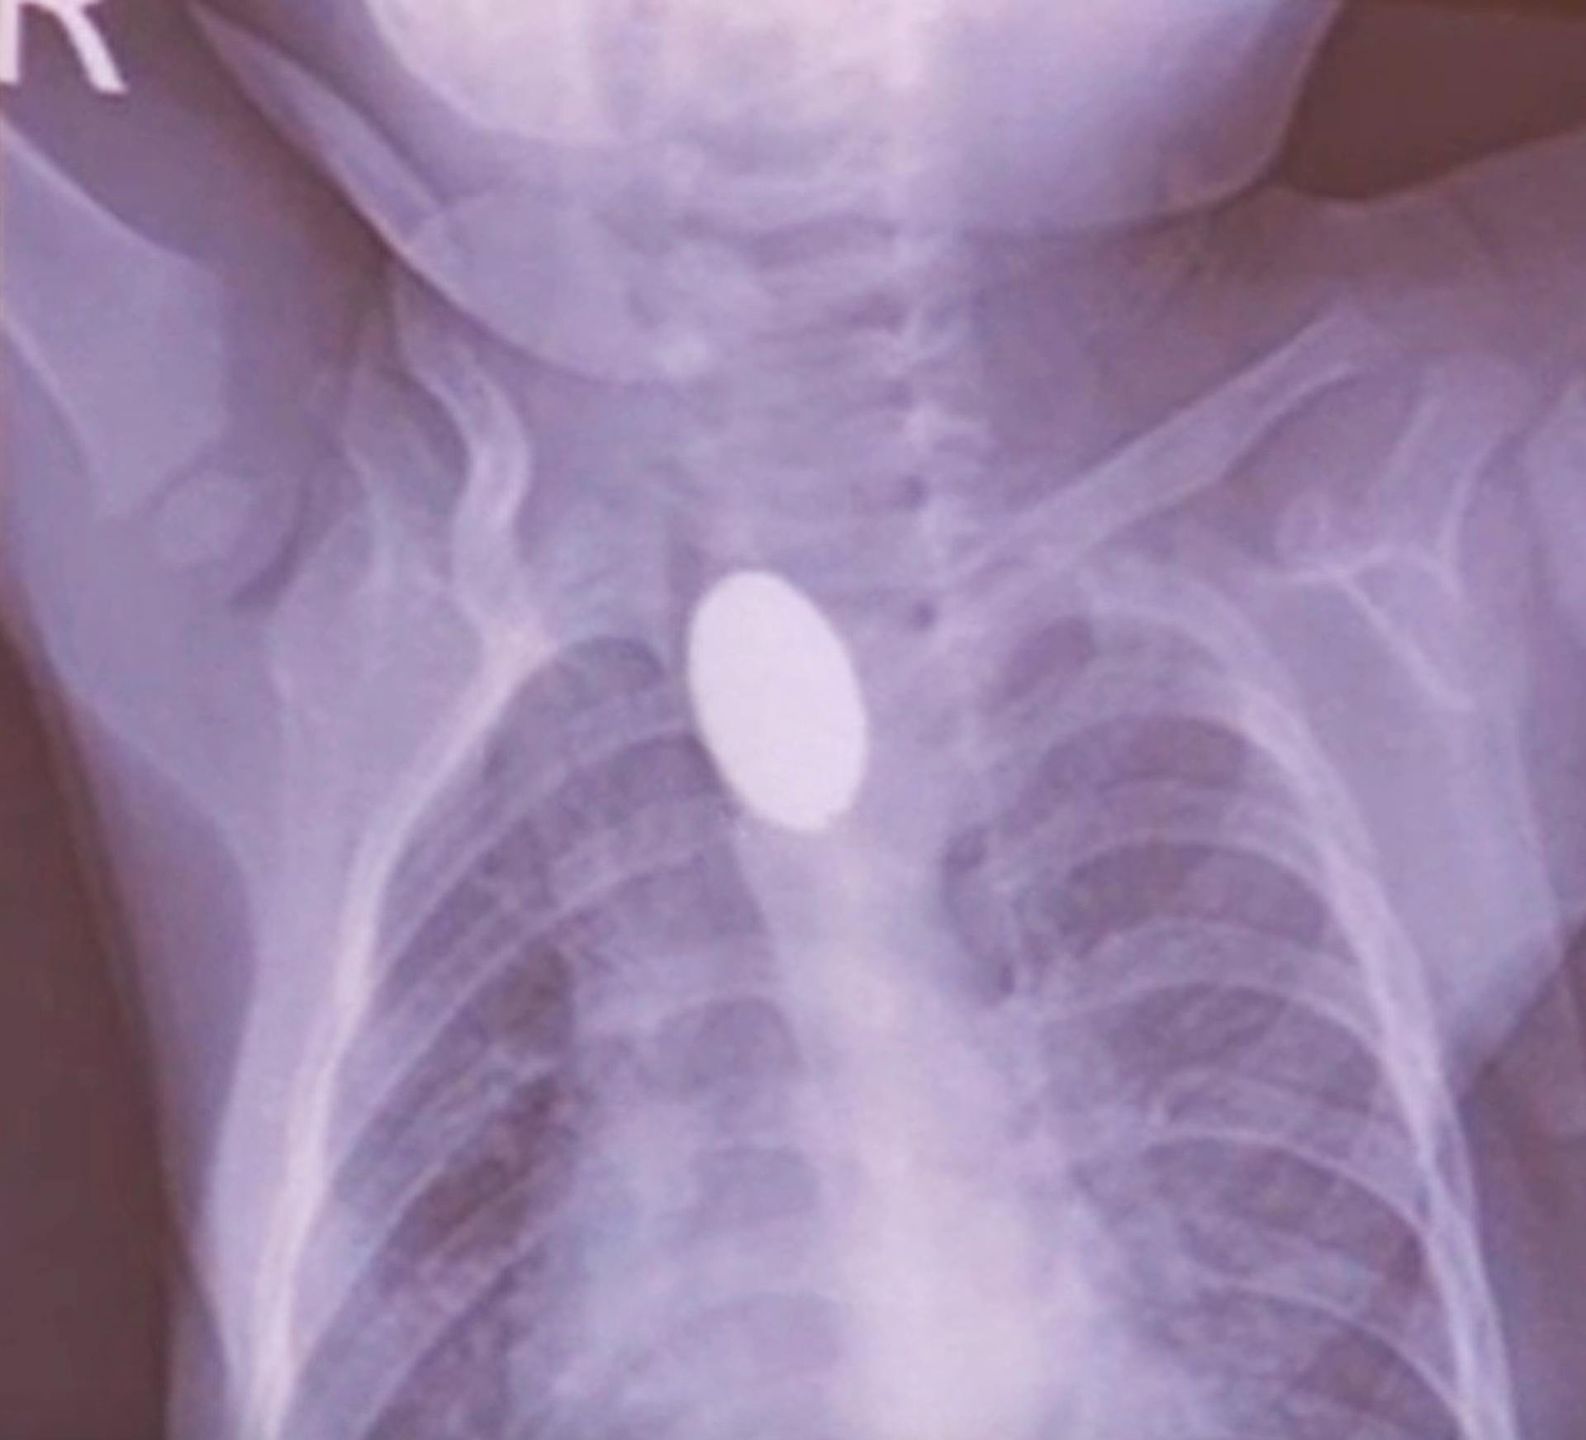

Mama chłopca nie zauważyła, co się stało, ale gdy tylko zorientowała się, że coś jest nie tak, zabrała go do szpitala uniwersyteckiego Elazig Firat. W przeprowadzonej kontroli stwierdzono, że bateria utknęła w przełyku i spowodowała oparzenie. Wkrótce podjęto dezycję o usunięciu jej metodą endoskopową.

Dr Yasar Dogan, który zajął się chłopcem, zamarł, gdy wykonał rentgen. Wiedział, że musi działać szybko. Na szczęście był w stanie wyjąć przedmiot z jego przełyku za pomocą endoskopu, ale zauważył, że malec doznał oparzeń w miejscu, w którym bateria się zatrzymała.

"Zauważyłem poważne oparzenia przełyku po usunięciu baterii metodą endoskopową. Zostanie wprowadzona specjalna metoda karmienia, tak by móc kontrolować stan gojenia ran dziecka, czy nie wystąpi infekcja"- powiedział dr Dogan.